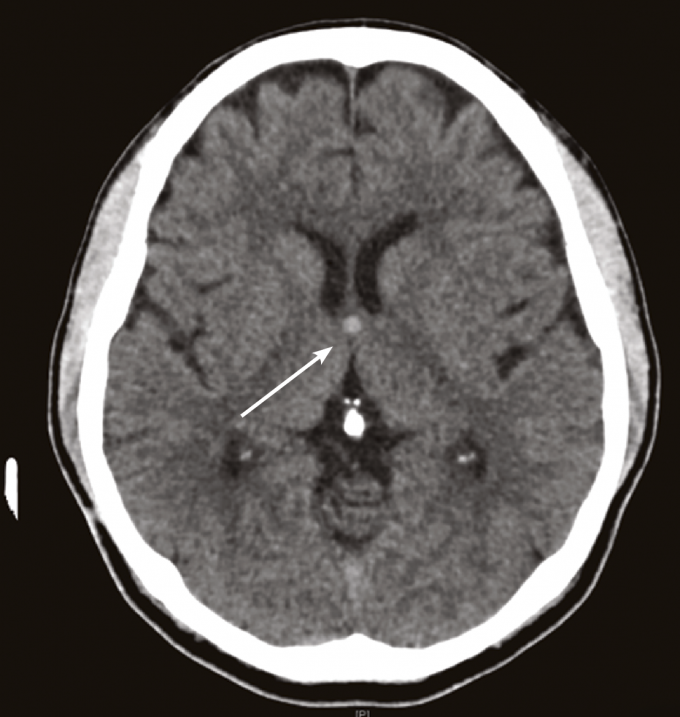

Varying imaging features of colloid cysts. (A) Axial CT scan and (B Colloid Cyst Management Colloid cysts of the third ventricle are histologically benign lesions that can cause obstructive hydrocephalus and death. The overall approach from diagnosis to management to definitive treatment of a colloid cyst requires an interdisciplinary. Asymptomatic lesions may be managed conservatively with routine. An individual with a suspected or diagnosed colloid cyst should be referred to a neurosurgeon for evaluation and. Colloid Cyst Management.